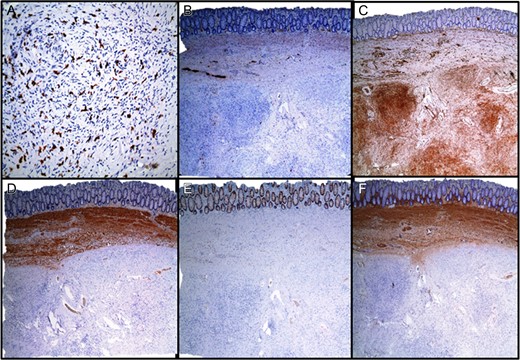

On excision, the lesion was grossly a 4.2 cm encapsulated, tan-pink, soft mass with golden to tan firm, nodular cut-surfaces (Fig. 3A). There was evidence of tumor <1 mm from the resection margin but without evidence of tumor transection. Histopathological examination revealed a variably cellular, well-circumscribed submucosal lesion (Fig. 3B) with bland spindle cells (Fig. 3C), lymphocytes, plasma cells and eosinophils (Fig. 3D). No pleomorphism, mitoses or necroses were identified. Areas with thick-walled vessels were also seen (Fig. 3D). The differential diagnoses included inflammatory fibroid polyp, gastrointestinal stromal tumor (GIST), schwannoma, leiomyoma, perineuroma and solitary fibrous tumor. Immunohistochemistry was negative for CD117, DOG1, Calponin, EMA, SMA, STAT6 and S100. CD34 was found to be positive (Fig. 4). The morphological and immunohistochemical findings supported the diagnosis of inflammatory fibroid polyp. In order to rule out the possibility of GIST, further molecular studies were performed which revealed no mutations in KIT exons 9, 11, 13 and 17 or PDGFRA exons 12, 14 and 18.

The lesion was grossly a tan-pink, soft mass with golden to tan firm, nodular cut-surfaces ( A). Histopathological examination revealed a variably cellular, well-circumscribed submucosal lesion (B) with bland spindle cells ( C), lymphocytes, plasma cells and eosinophils (D). No pleomorphism, mitoses or necroses were identified. Areas with thick-walled vessels were also seen (D).

Immunohistochemical staining. (A) CD117, (B) S100, (C) CD34, (D) CALPONIN, (E) EMA, (F) SMA.